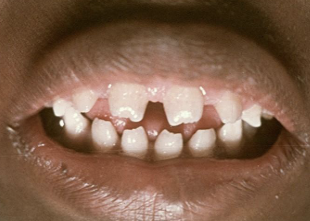

intra-oral presentation of congenital syphilis;1st molars develop irregular nodules of enamel on occlusal surface

mulberry molars

intra-oral presentation of congenital syphilis; “screwdriver” incisor

hutchinson’s incisor

H & N effects of congenital syphilis

mental degeneration, cartilage, septal destruction of nose (saddle nose), blindness, deafness (CN 8)